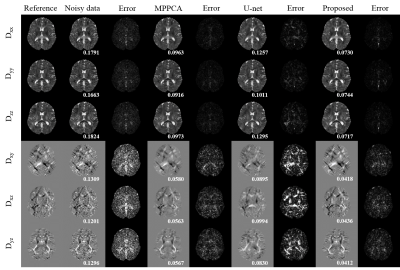

In Fig.3, the dMRI data’s diffusion gradient scheme is different from the training data. The six element maps of DTI field obtained in proposed method are less noisy with more accurate details preserved and have the lowest RMSE. In Fig 4, the real dMRI data’s acquisition scheme is different from the train data. Compared with MPPCA, FA and MD obtained in proposed method are less noisy. Both results prove that this method has a strong generalization ability.

Fig.3 The six element maps of DTI tensor field obtained from different methods and corresponding error maps. The dMRI data has one b = 0 mm/s2 volume and six b = 1000 mm/s2 volumes with noise level of 0.01. The DTI tensor field of MPPCA was estimated from corresponding denoised dMRI data. The U-net represents a 3D U-net which used dMRI data as train data. The RMSE is shown in the bottom of each element.